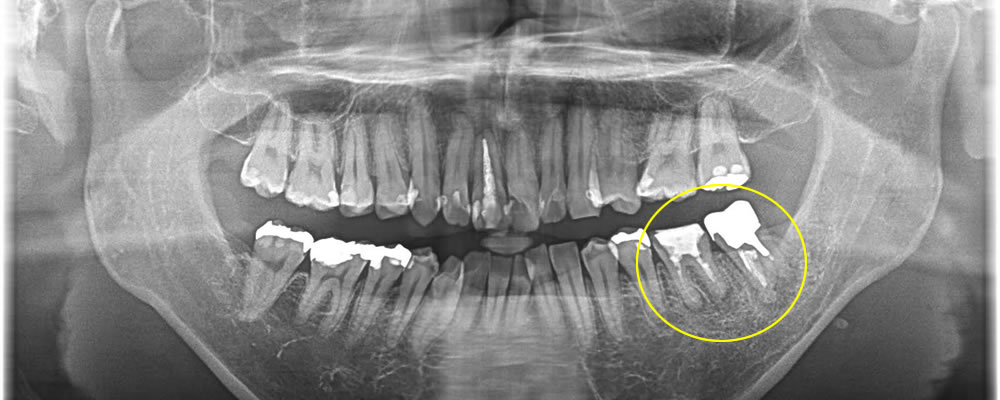

マウスピース矯正(インビザライン)で前歯の叢生を改善した症例

年齢

30代

性別

男性

症例を見る